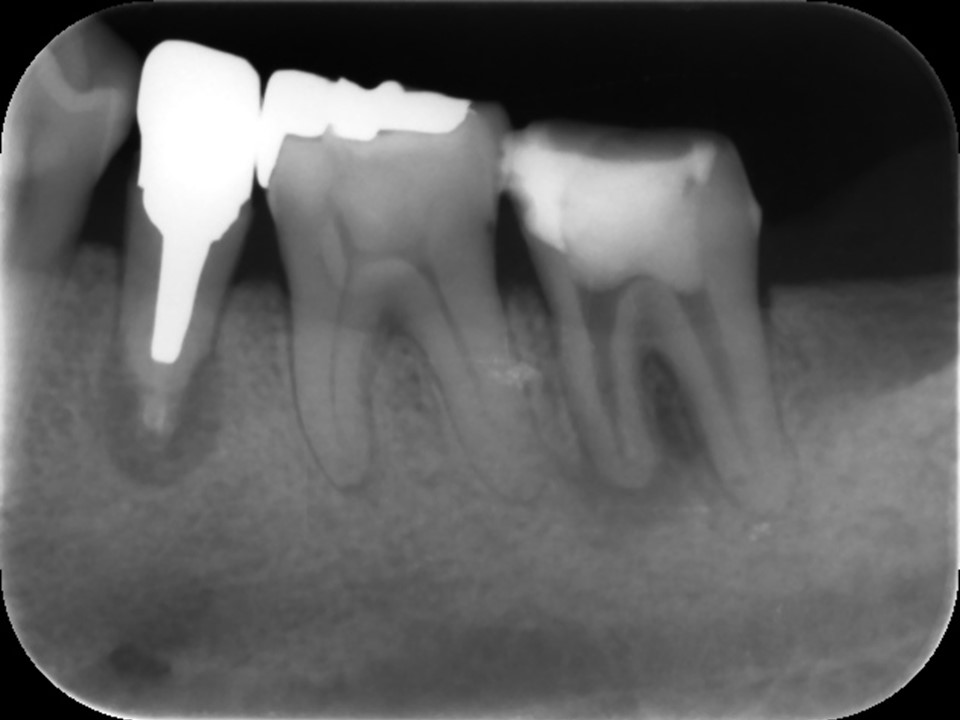

当該の左下7番の奥歯はクラウンで被せてありましたが、頬側に歯茎の腫れ(フィステル、サイナストラクト)を認めました。レントゲンおよびCTによる診査を行ったところ、すでに根管治療が施してあるものの根管充填が不十分で、根尖病変を生じていました(下写真)。また、歯根の先端部分にはファイルと思われる器具の破折片を認めました(矢印)。根管内部へのバクテリアの感染による慢性化膿性根尖性歯周炎と診断し、再根管治療をおこなうことにしました。

治療前のレントゲンおよびCT画像です。当該歯はすでに根管治療が施してあり、根尖部には根尖病変によるX線透過像を認めます。

また、根尖部にはファイルと思われる器具の残存を認めます(矢印)。